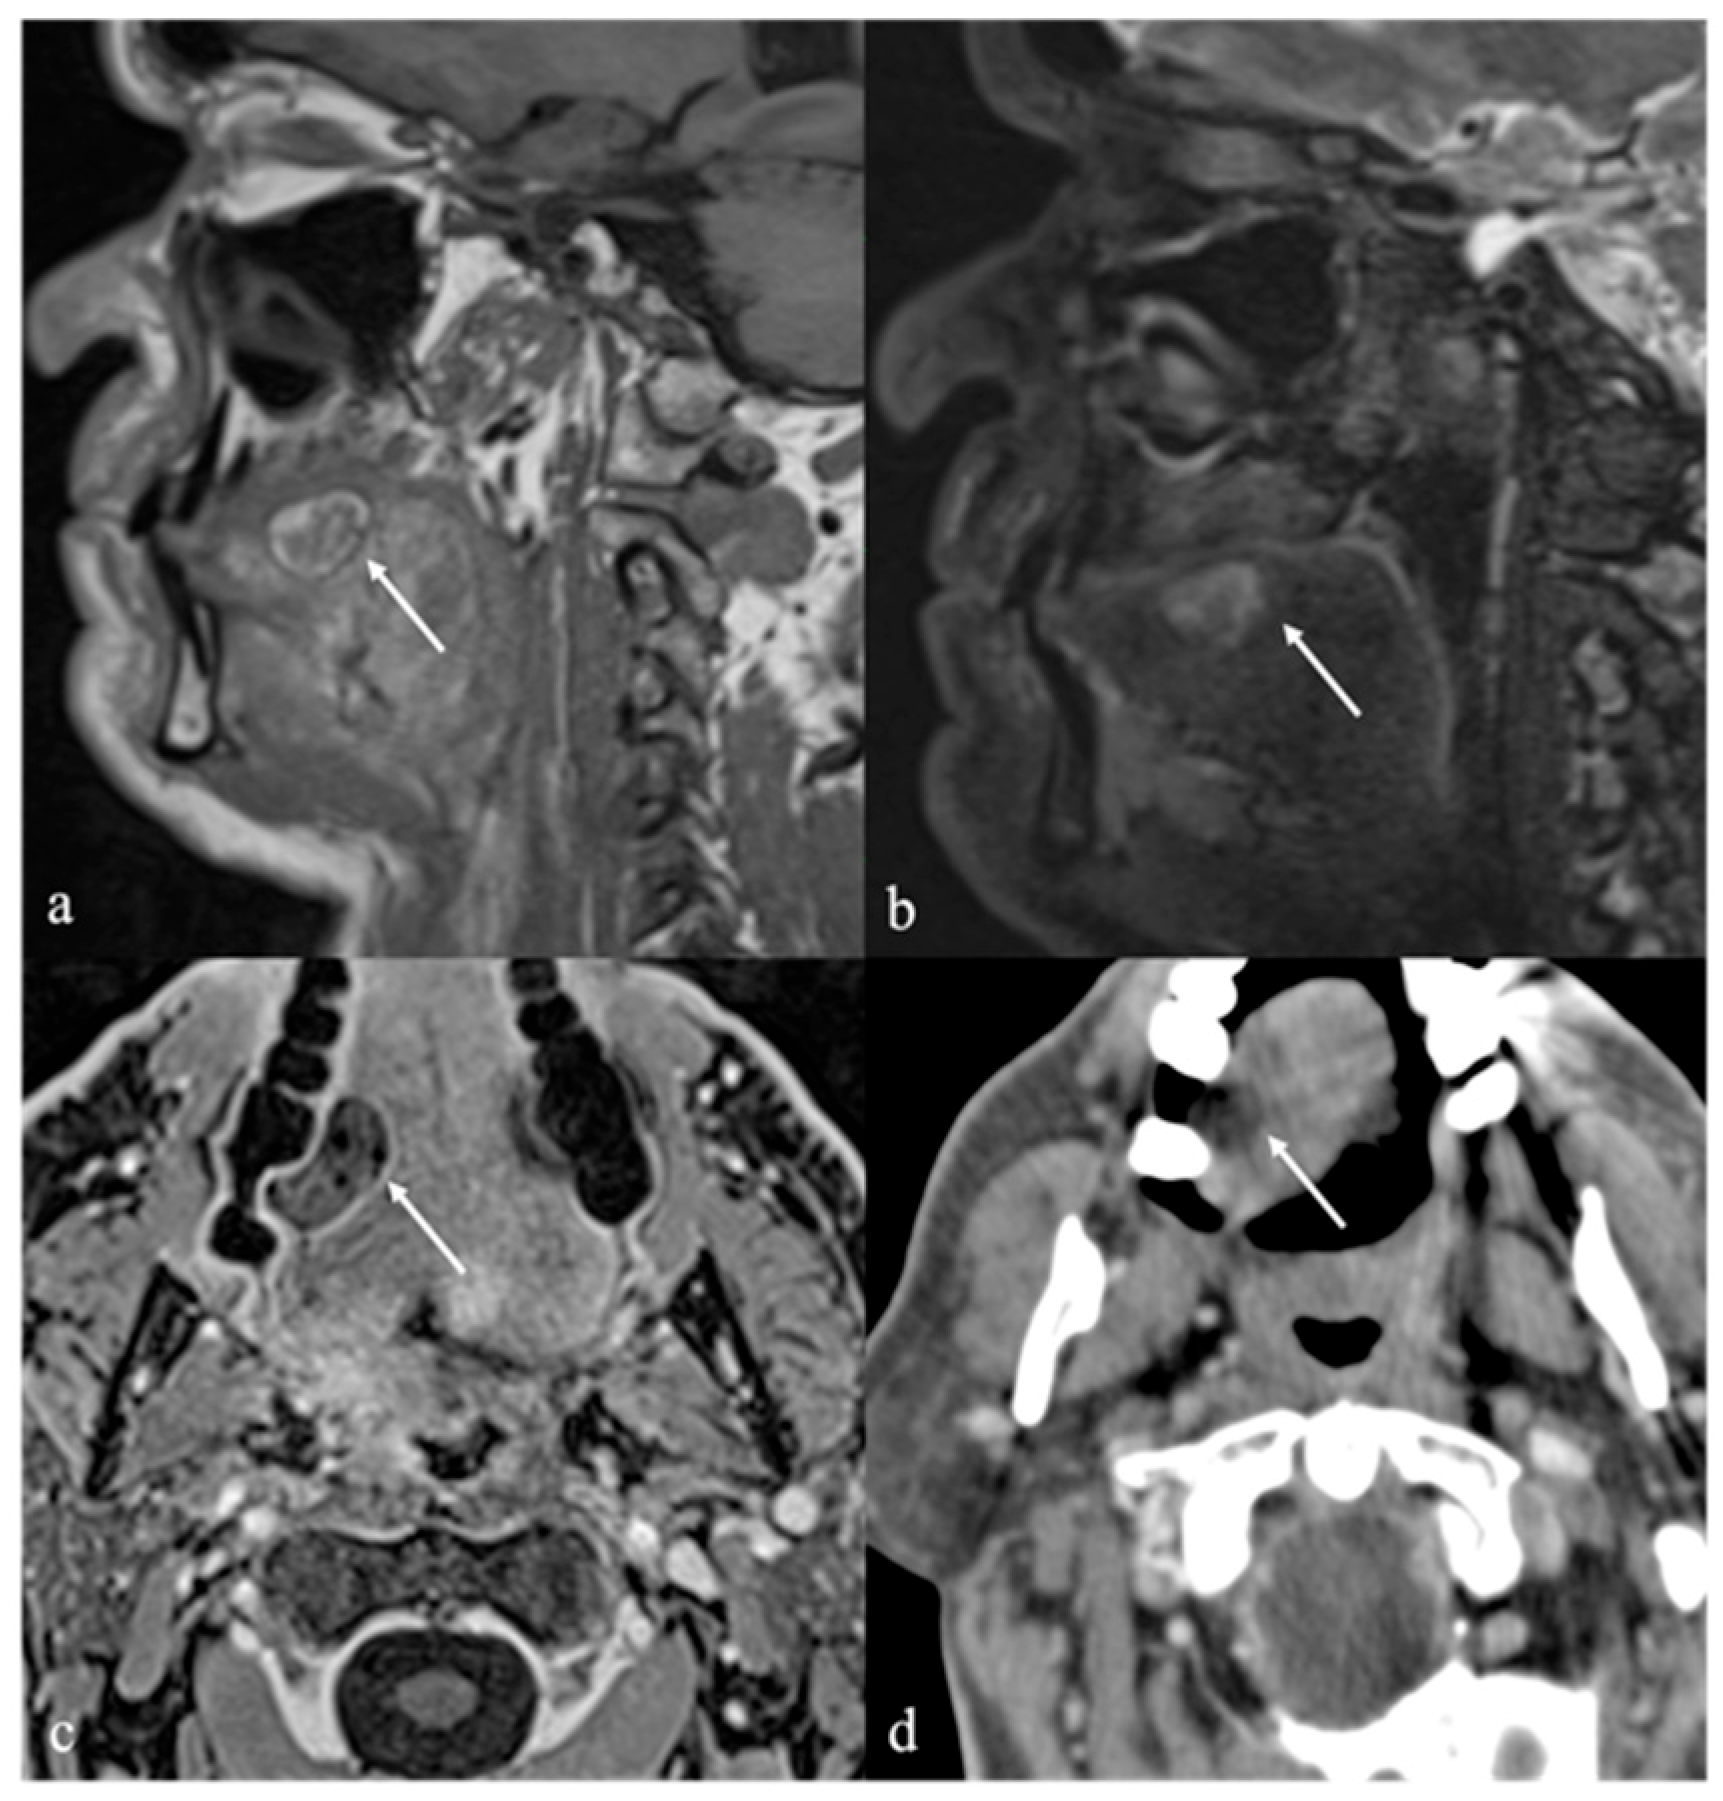

6. Dermoid Cysts

| Dermoid cyst [1,13,14] | CT: free fat and calcified corpuscles (“sack of marbles” sign) | Vascular malformation, epidermoid cysts, lipoma |

| Epidermoid cyst [14] | MRI: high SI on DWI, and restricted diffusion with low values on ADC map | Vascular malformation, dermoid cysts |